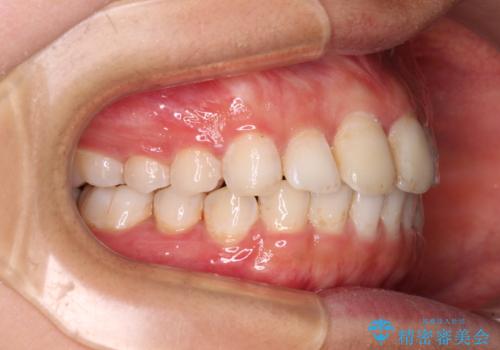

前歯の捻れを改善 インビザラインによる矯正治療

- 前歯の翼状捻転を気にして来院された患者様です。

全体的に叢生は軽度であったため、インビザラインにて矯正治療を行うこととしました。

前歯の幅の大きさも気になっていたため、IPRにより叢生を解消するとともに、歯の大きさも改善しました。